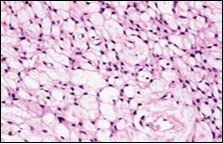

Figure 1.Soft tissue perineurioma with fascicles of bipolar neural cells with elongated cytoplasmic processes, wavy nuclei and an admixture of collagen fibres 11.

Figure 2.Soft tissue perineurioma with lamellar bundles of neural cells demonstrating elongated cytoplasmic processes, wavy, slender nuclei and admixed collagen fibres 12.

Figure 3.Soft tissue perineurioma with whorls and fascicles of neural cells displaying wavy nuclei, elongated cytoplasmic fibrils and intermingling of collagen fibres 13.

Figure 4.Soft tissue perineurioma composed of whorls and perivascular aggregates of neural cells with bipolar cytoplasmic processes, wavy, slender nuclei and commingled collagen fibres 13.

Figure 5.Soft tissue perineurioma /schwannoma with whorls and lamellae of neural cells with bipolar cytoplasmic processes, wavy nuclei and intermingled collagen fibres 14.

Figure 6.Soft tissue perineurioma with foci of spindle cells with wavy nuclei and an admixture of myxoid and collagenous stroma 15.

Figure 7.Soft tissue perineurioma with an abundance of collagen fibrils intermixed with a neural element with bipolar cells with elongated cytoplasm and wavy nuclei 16.

Figure 8.Soft tissue perineurioma with neural cells exemplifying elongated cytoplasmic processes, slender, wavy nuclei and an abundance of collagenous stroma 17.

Figure 9.Soft tissue perineurioma with plentiful collagenous fibrils intermixed with lamellar neural tissue with elongated cytoplasmic extensions and wavy, pointed nuclei 18.

Figure 10.Soft tissue perineurioma demonstrating immune reactivity to epithelial membrane antigen EMA18.

Figure 11.Soft tissue perineurioma with whorls of neural cells delineating spindle cells with bipolar cytoplasm and wavy nuclei and an admixture of collagen bundles 19.